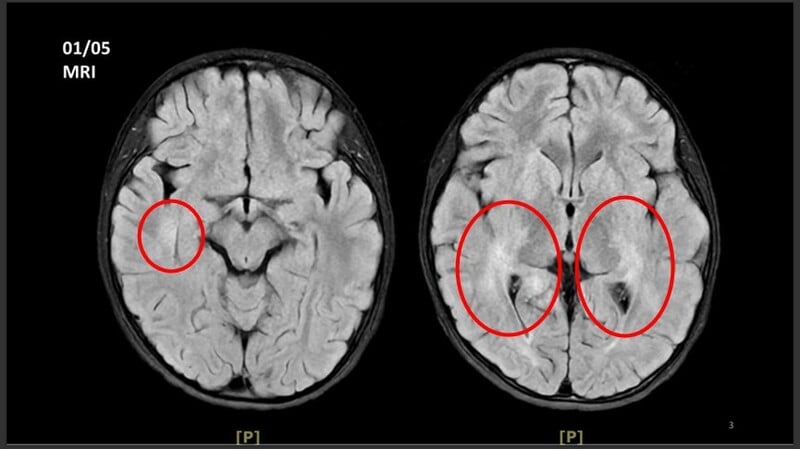

王傳育主任指出,女童當時血壓明顯偏高,心跳也較慢,醫療團隊擔心已有腦壓升高或顱內病變,立即安排住院,並同步給予降低腦壓治療與核磁共振掃描。檢查結果顯示,小腦、視丘及大腦白質、皮質下都可見異常訊號,符合急性散播性腦脊髓炎的影像表現。

醫療團隊進一步將血液送往台大醫院檢驗自體免疫抗體,最後證實為MOG抗體陽性相關疾病。王傳育主任說明,MOGAD是一種自體免疫性脫髓鞘疾病,當異常抗體攻擊腦部、視神經或脊髓外層的髓鞘時,就可能造成神經發炎與功能異常。九歲以下兒童較常以ADEM形式表現,較大的孩子或成人則可能出現視神經炎、脊髓炎,甚至肢體麻痺等較嚴重症狀。